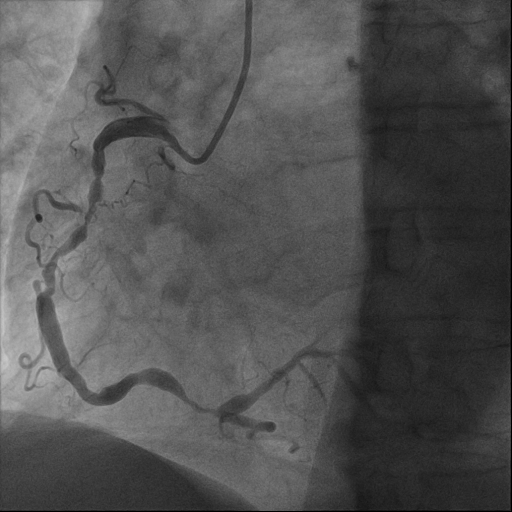

经过胸痛中心绿色通道,综合内科主任蔡国才带领的介入团队通过穿刺右侧桡动脉,将纤细的造影导管送入血管到达冠状动脉开口。屏幕上清晰显示:前降支中段一处99%的狭窄正在“作祟”——这正是导致老人胸痛的“罪魁祸首”。

(左:术前 右:术后)

经过团队的精准操作,医护配合,迅速将导丝通过狭窄病变,沿着导丝送入球囊导管,从患者进入医院大门到导丝通过仅仅过去32分钟(D-to-W),狭窄的冠状动脉血管被成功扩张,并顺利植入支架,冠脉狭窄血管处的血流瞬间恢复正常。刘婆婆胸痛症状完全缓解,生命体征平稳,手术结束,家属激动地握住医护人员的手,连声道谢。